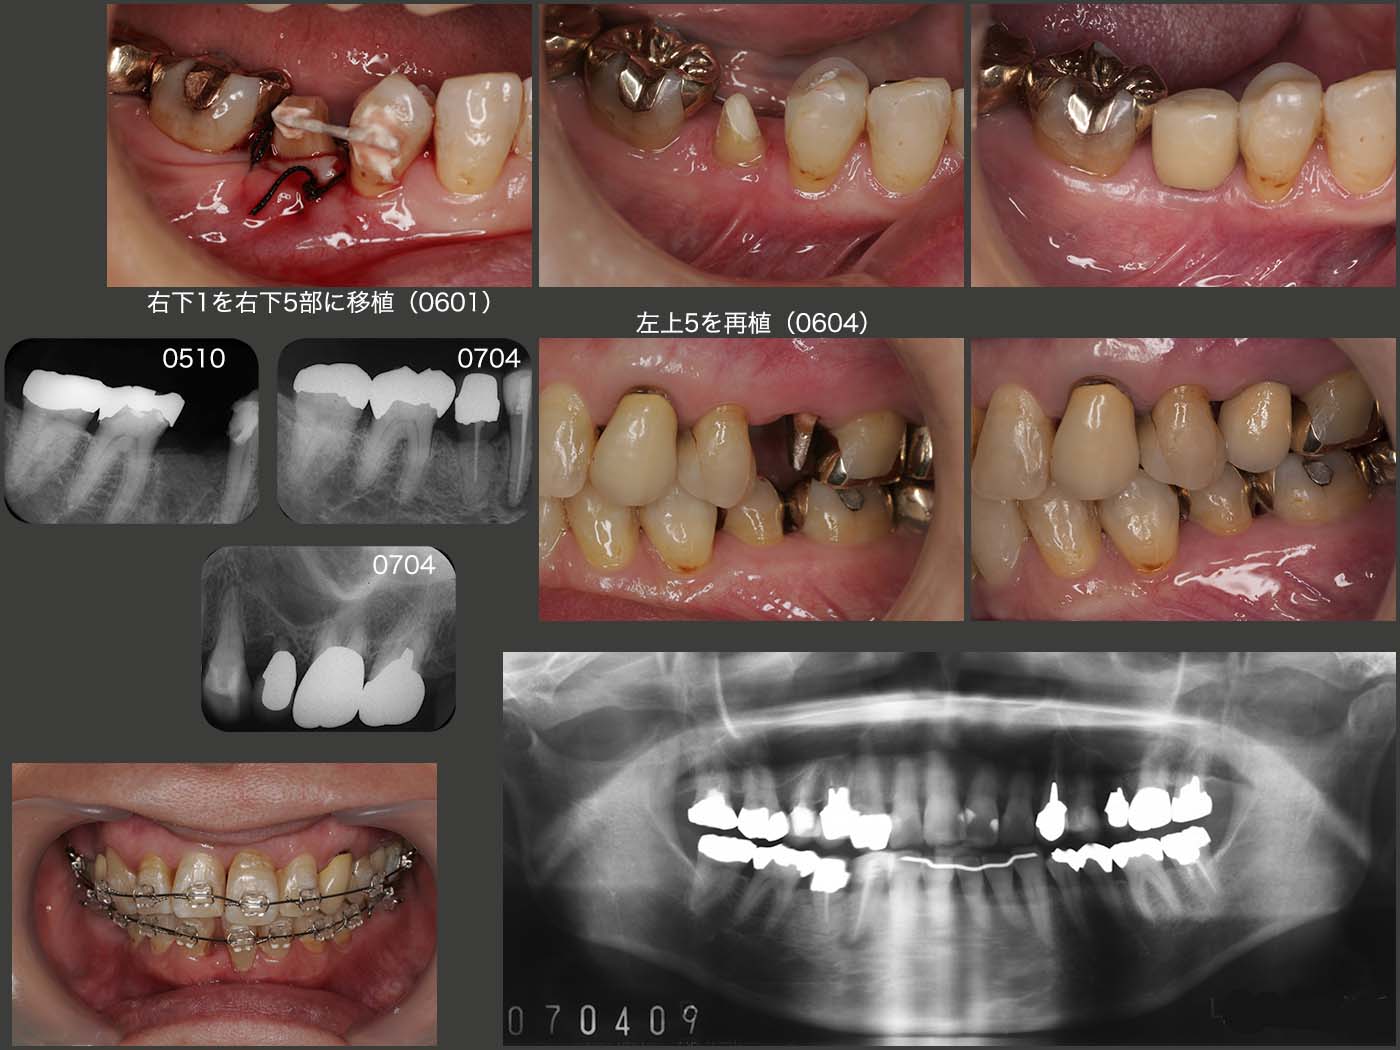

初診は2005年4月,61歳女性.主訴は左上5のクラウン脱落.まず右下4のう蝕処置(生切・09年抜髄)および歯周基本治療を行った.スライドは05年10月の状態であるが,左上5は矯正的挺出中,右下5は歯根破折にて抜歯した直後.

2006年1月に右下1を右下5部に移植した.左上5は矯正的挺出終了後暫くしてフィステルが生じてしまった.感染根管処置を施したが,根尖が開かなかったので,06年4月に再植を行った.またドナーとして抜去した右下1の空隙を埋めるため,さらに上顎前歯の審美的改善を期待して歯科矯正を行った.07年4月に治療は全て終了した.

この当時は,歯を連結固定すると清掃性が落ちることから,極力連結固定を避ける気持ちが強かった.もちろん暫間被覆冠で咀嚼できる等の反応をみて判断していたが,再植,移植した歯は若干動揺が残るので,当該歯には大きい咬合力が加わらないから安全であると高をくくっていた.このケースも暫く反応をみたが特に問題がなかったので,再植した左上5および移植した右下5を単独植立のままとした.